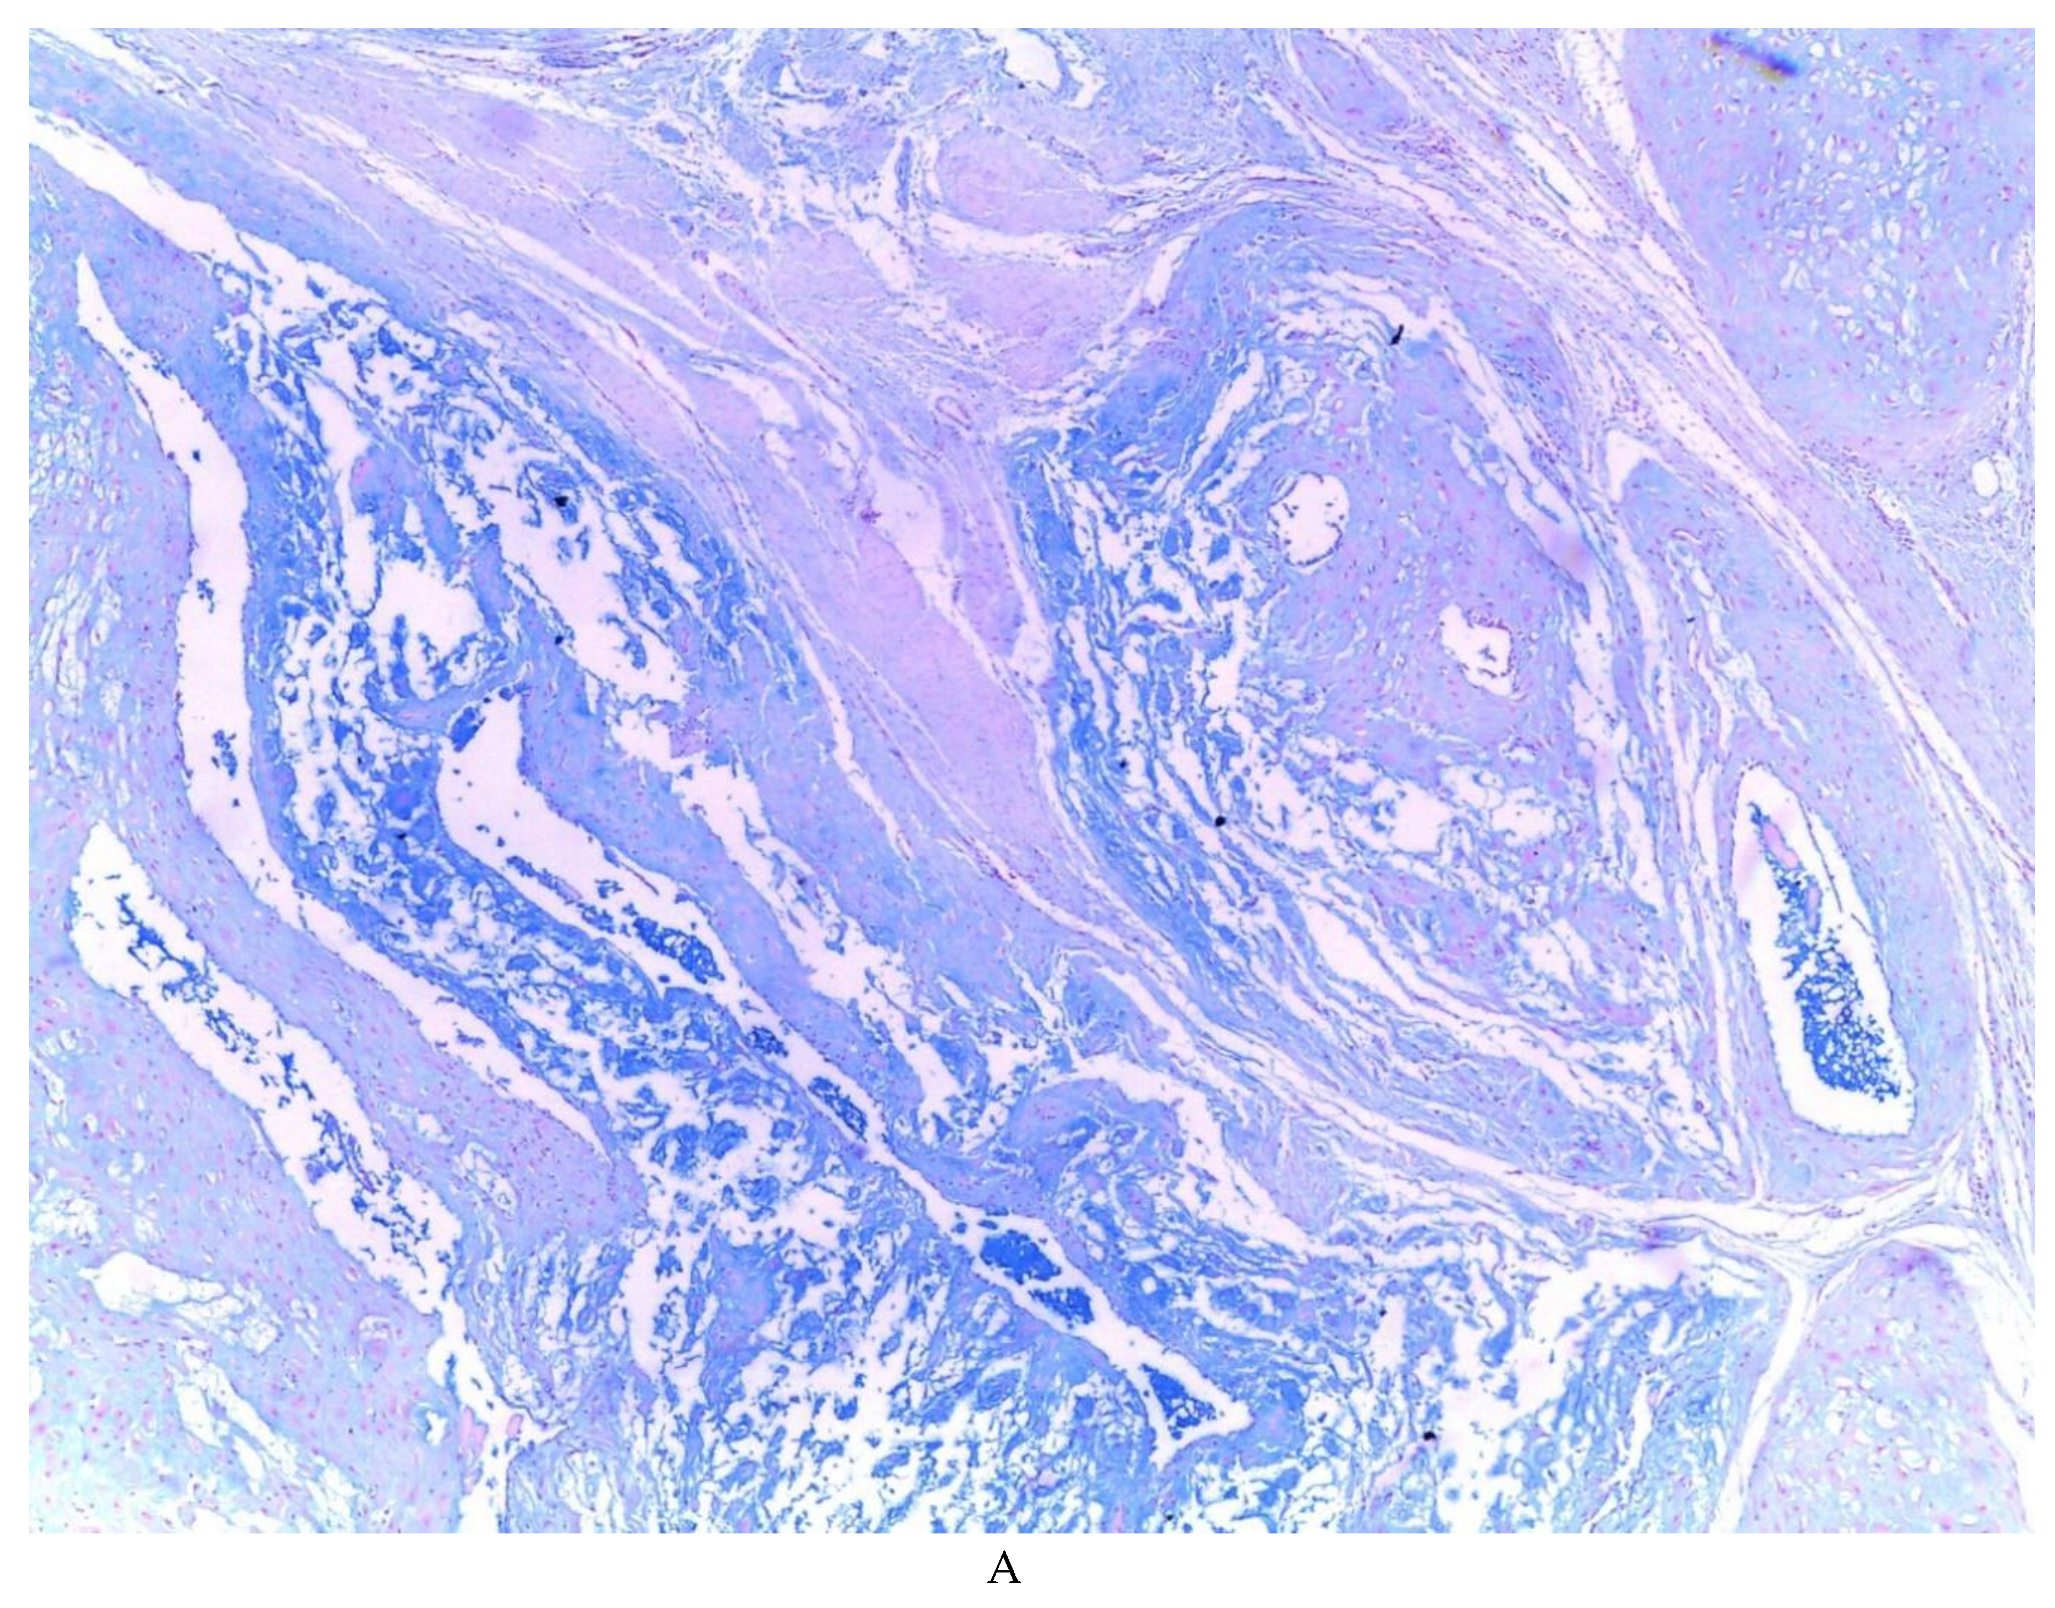

776 cases of endometriosis were collected between the two institutions participating in the study, in different anatomical sites (Table 1, Figure 1), in which 54 of them presented a myxoid stroma greater than 50% with respect to the cellularity of the samples. and that represent 6.95% of the total endometriosis examined with the following locations: omentum (4/20), ileum (2/4), ovary (14/216), parametria (2/9), soft tissues (28/235), salpingus (3/77), bladder (1/4). The clinical records of these patients were consulted and the common denominator was that the women were in the surgical (41/57) or physiological (7/39) puerperium in a period of time from 24 hours postpartum to six months after said event. Macroscopically, two different lesions were observed: the first one, which is the most frequent, presents as a non-encapsulated lesion with pushing edges of a fibromyxoid appearance; the second and less frequent, a well-defined lesion, partially or totally encapsulated, the cut surface is shiny, gelatinous in appearance, multilobed, light brown to brown in color with focal areas of recent and old hemorrhage, these lobes are separated by fibrous septa (Figure 2). Histologically, it was found in all the samples evaluated at least 50% of myxoid stroma with some fine connective tissue septa with proliferation of stromal cells (Figure 3A), which present four variants in their shape: (1) Epithelioid stromal cells of wide eosinophilic cytoplasm with round nucleus with small nucleolus (Figure 3B), (2) Pseudolipoblast-type stromal cells with moderate cytoplasm, multivacuolated in their cytoplasm that can present eosinophils or be clear cytoplasm, with central nuclei of granular chromatin (Figure 3C), (3) “pseudosignet ring” stromal cells with nucleus and cytoplasm rejected to the periphery giving the aforementioned appearance (Figure 3D) and (4) immersed spindle cells with small nucleus and barely visible nucleolus (Figure 3E); Among these cells, the epithelial component is observed, which is forming tubules that vary in diameter, ranging from small tubules and large cystic dilations of the gland that presents a layer of low cubic to cylindrical epithelium, generally with an atrophic appearance (Figure 3F). Hyaline globules were found in the glandular lumens (Figure 3G). The extracellular matrix showed a composition by glusocaminoglycans evidenced in 100% of the cases by staining present for AA (Figure 4A–C), but without staining for PAS; however, the latter stained on proteinaceous globular material in the lumen of the endometrial glands (Figure 4D). Immunohistochemistry for CD10 was positive in 100% of the stromal cells with a mild to moderate reaction in the cytoplasm and membrane with a decidual appearance (Figure 5A,B). The ER and PR showed nuclear expression in 100% of the cases, with greater intensity in the ER (Figure 5C) than in the RP (Figure 5D); both hormone receptors were expressed on endometrial epithelial cells as well as on stromal cells. The cases of myxoid endometriosis examined did not present cytological atypia suggesting any precursor lesion of epithelial or stromal origin.

Figure 4. Myxoid endometriosis – histochemical stains; A-C) Alcian blue. D) PAS, note the staining of the hyaline globules.